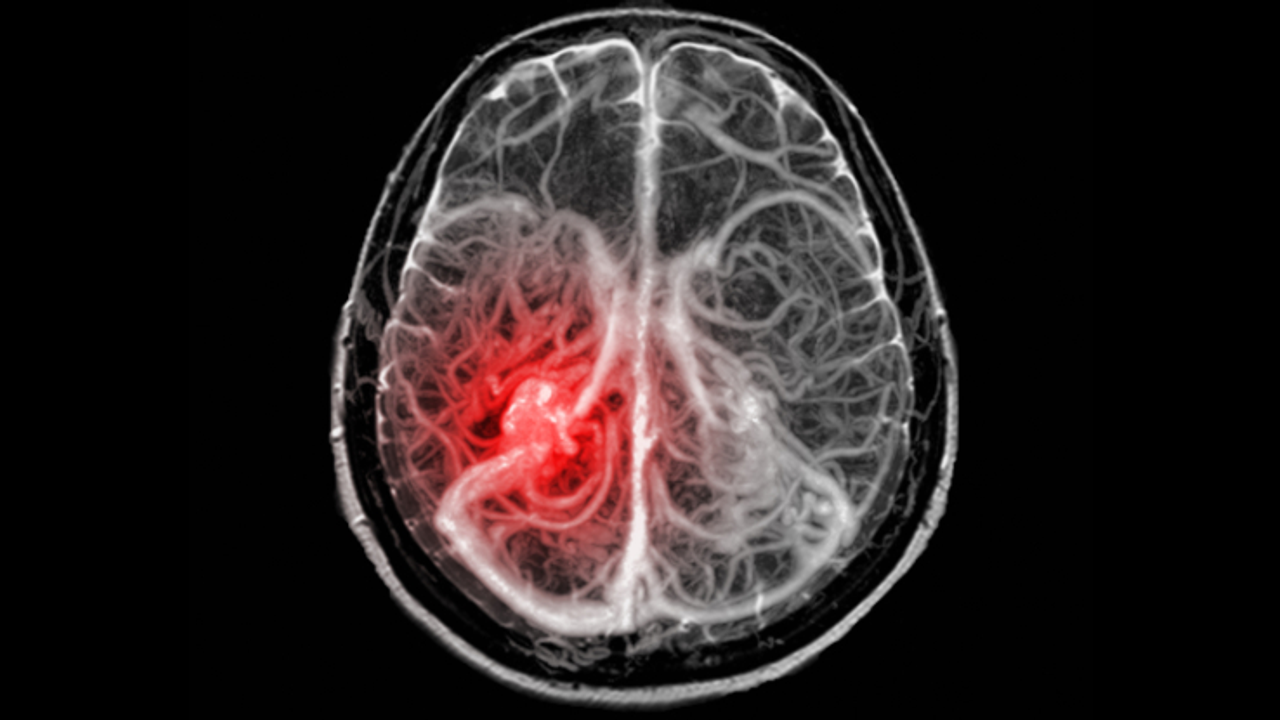

ABD'nin Utah eyaletinde, hava kalitesinin oldukça düşük olduğu Wasatch Front bölgesinde yapılan küçük çaplı bir çalışma, kirli havaya uzun süre maruz kalmanın beyin kanaması riskini artırabileceğini ortaya koydu. Utah Üniversitesi'nden beyin cerrahı Robert Rennert liderliğindeki araştırma, beş yıl boyunca hastaneye başvuran 70 beyin kanaması hastasının çevresel maruziyet geçmişini inceledi.

Araştırmaya göre, havadaki ince partikül madde (PM2.5) seviyelerinin zirveye çıktığı dönemlerden 3 ila 6 ay sonra, beyin anevrizmalarında yırtılma vakaları anlamlı şekilde artıyor.

Araştırmacılar, kısa süreli değil, uzun vadeli maruziyetin vücutta hücresel hasar birikimine neden olduğunu, DNA onarım mekanizmalarını zayıflattığını ve bağışıklık sistemini iltihabi tepkilere karşı daha hassas hale getirdiğini belirtiyor. Bu etkiler zamanla beyin damarlarının duvarlarını zayıflatıp yırtılmalara yol açabiliyor.